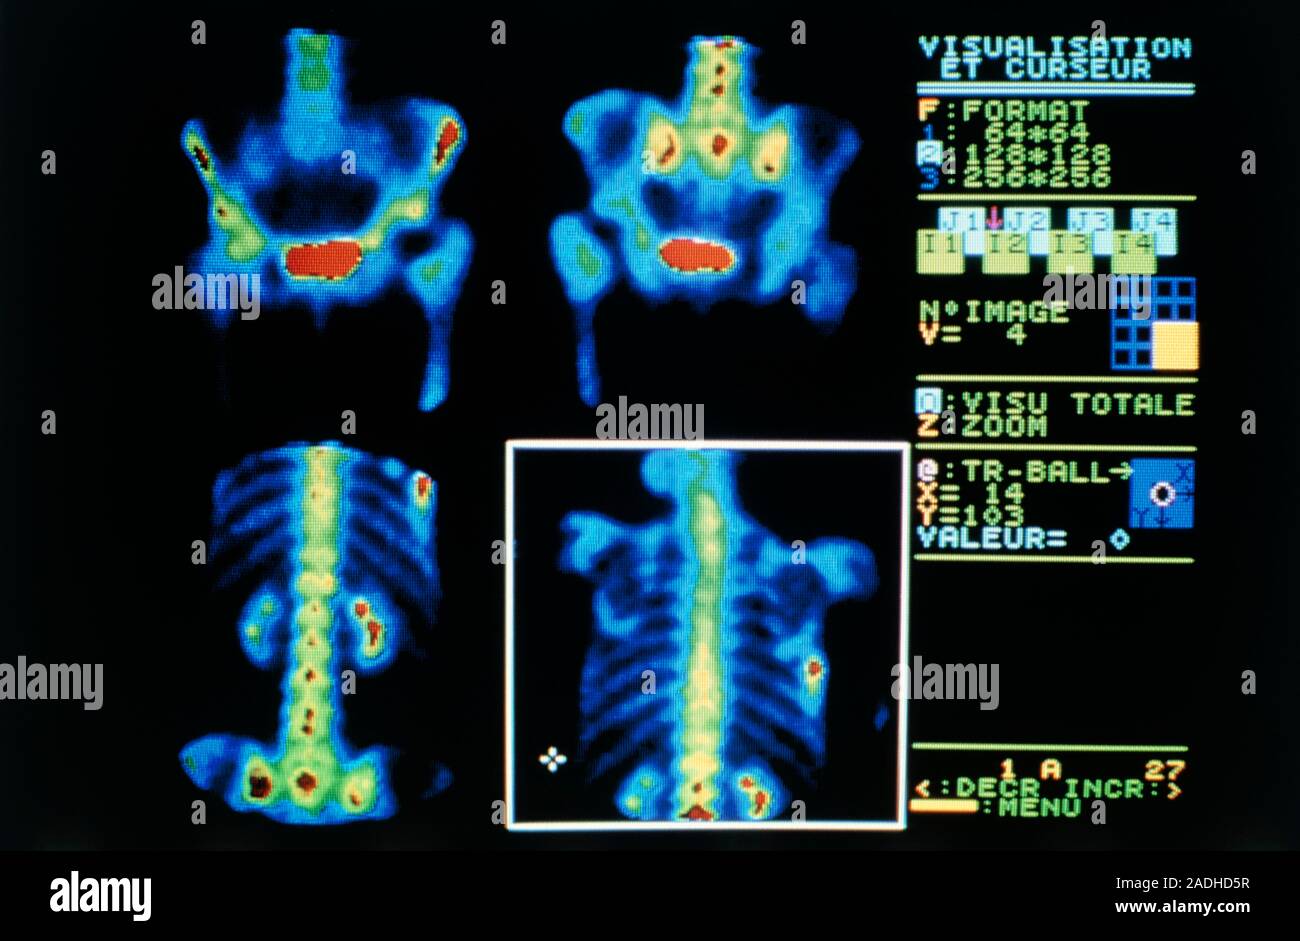

Gamma camera scans of a person suffering from multiple metastastic Gamma Camera Artifacts — four gamma cameras were used to acquire planar images of four‐quadrant bar phantoms and projection. A technologist case study” (5) was. Become familiar with routine performance tests (daily,. Beth israel deaconess medical center department of radiology boston, ma usa. — gamma cameras are complex pieces of equipment which rely on sophisticated hardware and software in. gamma. Gamma Camera Artifacts.